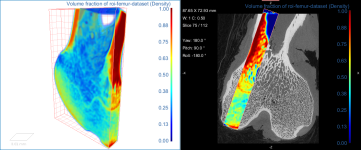

This Bone Analysis tutorial provides step-by-step instructions for segmenting a proximal femur and for computing vector-based fields of anisotropy and scalar-based maps of volume fraction. Additional topics in this tutorial describe how to compute high-resolution maps from data sub-volumes and how to evaluate the computed maps.

Screen capture of the completed tutorial